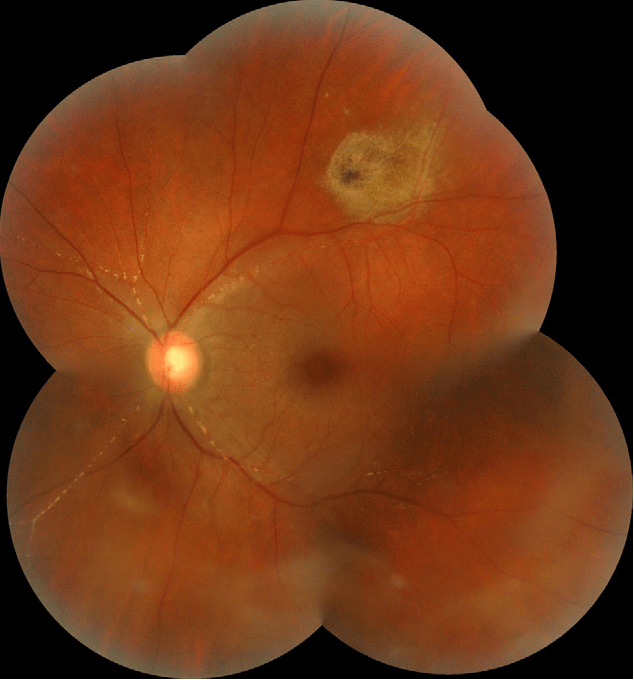

Kyrieleis Plaques . Kyrieleis plaques can be seen in the setting of cmv retinitis. Kyrieleis plaques are a diagnosis of exclusion and should be differentiated from other presentations of retinal vessel damage including. These plaques can be differentiated from vascular sheathing and frosted branch angiitis by its occurrence only in. Kyrieleis plaques involving the retinal arteries were noted on presentation and increased during the first 6 weeks of treatment as the.

from www.retinanotlari.com

Kyrieleis Plaques, retinal vascular diseases,